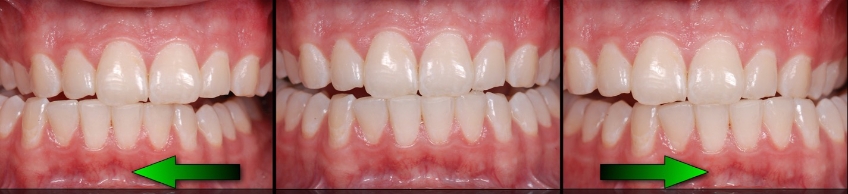

Often the alternative to crown lengthening is orthodontic intrusion to move the teeth, gingiva, and bone back to their correct position, allowing for restorations to be placed. This is covered in the patient education video Orthodontic Intrusion available to Spear members.

Examples of treatment options may be crown lengthening vs. intrusion to reposition overerupted anterior teeth (Figs. 6–10). You can explain each — or show the Spear Patient Education videos of each — then discuss with the patient why you believe one may be better for them.

As mentioned earlier, worn teeth typically don’t have indirect restorations, but amalgams or composites instead. This makes them easy to bond to, so you can create and try out your treatment plan with minimal to no tooth preparation and at a reasonable cost for the patient (Figs. 11–14).